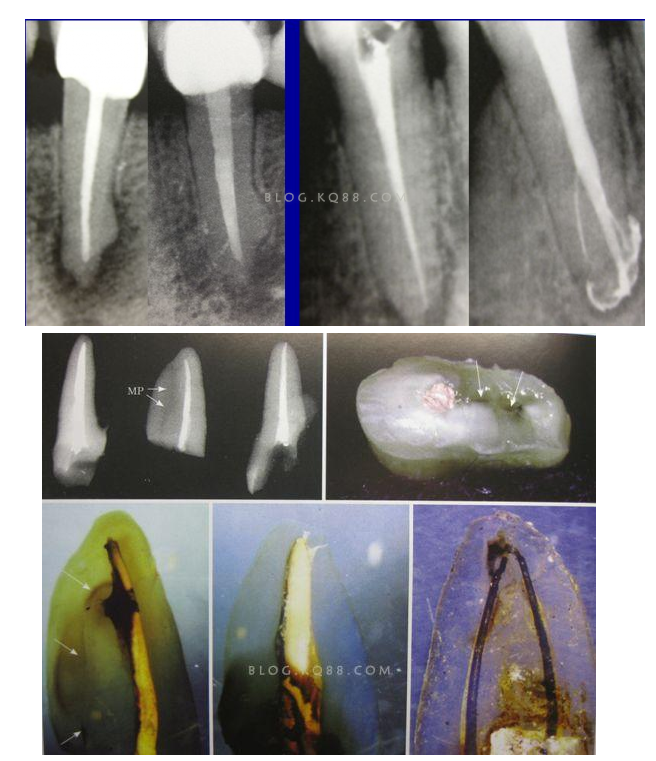

3、感染控制決定成敗 根管治療中感染控制的徹底程度直接決定根管治療的成功率,對(duì)主根管、牙本質(zhì)小管、側(cè)支根管的控制同等重要;完善根管治療后的患牙失敗主要原因是根管系統(tǒng)的頑固的感染或根尖周頑固的根管外細(xì)菌感染,當(dāng)然也有可能是非細(xì)菌性因素,但根管內(nèi)的感染占主要原因。在高效率的機(jī)械預(yù)備根管時(shí),一定要用專(zhuān)用的側(cè)方開(kāi)口針頭的注射器大量多次的沖洗根管,次氯酸鈉要加熱后使用,并及時(shí)補(bǔ)充新鮮的液體到根管系統(tǒng),EDTA液體的使用可以很好去除根管預(yù)備中產(chǎn)生的玷污層,1%的CHX液體可以在30秒內(nèi)殺滅糞腸球菌,并且有延緩作用,是優(yōu)秀的終末沖洗液。超聲蕩洗清理根管的效果要優(yōu)于手工沖洗。很多醫(yī)生考慮次氯酸鈉的濃度,其實(shí)次氯酸鈉沖洗液的濃度并不重要,重要的是沖洗的時(shí)間和次數(shù),更換新鮮液體的頻率和液體是否加熱。

4、敢于否定自己 有些病例看上去似乎是完美的,但是患者就是感覺(jué)有明顯的不適感,就應(yīng)該考慮是否有未處理的根管內(nèi)感染區(qū)域,分析是根管、峽部、分支、縫隙等原因后就要及時(shí)的采取措施,失敗病例的處理方法選擇非手術(shù)再治療還是手術(shù)再治療,一般首選非手術(shù)再治療,但要評(píng)估再治療的預(yù)期結(jié)果,如果非手術(shù)再治療的對(duì)患牙的創(chuàng)傷太大或預(yù)期效果不確定就考慮手術(shù)再治療,全面考慮分析后決定方法。要及時(shí)的決定下一步的處理方法。長(zhǎng)期的反復(fù)的復(fù)診觀(guān)察是沒(méi)有意義的,最后的結(jié)果是流失患者。

5、預(yù)備到多少號(hào)結(jié)束根管預(yù)備理想的情況應(yīng)該預(yù)備到多大錐度,多少號(hào),預(yù)備后根管空間是金字塔還是埃菲爾鐵塔。專(zhuān)家經(jīng)過(guò)離體牙根尖切片研究發(fā)現(xiàn)根尖狹窄部遠(yuǎn)比想象的要大,如果根管預(yù)備太小就會(huì)殘留感染物,根管的部分空間就不會(huì)預(yù)備到,殘留的感染物就會(huì)造成治療效果達(dá)不到預(yù)期目標(biāo)。只有做到了充分的預(yù)備,盡可能的多沖洗才會(huì)有好的結(jié)果。

根管治療要做到看清楚,去干凈,充恰滿(mǎn),封嚴(yán)密,就會(huì)達(dá)到期望的結(jié)果。2200年前的病例只充填了冠1/3可以理解、可以接受;2200年后的今天我們有先進(jìn)的設(shè)備和材料,就要充填出大錐度高密度的完美結(jié)果。理念決定技術(shù),標(biāo)準(zhǔn)決定技術(shù)的提高和進(jìn)步。